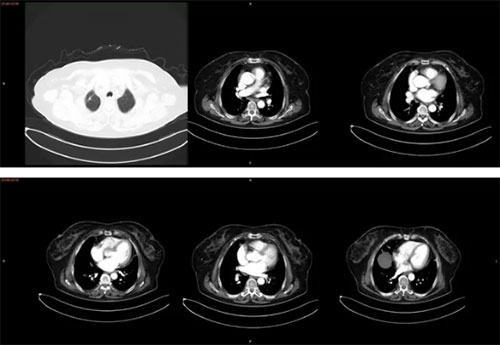

2017年10月治疗后患者CT提示病灶明显缩小,胸膜广泛转移病灶消失。

2018年10月查CT仍控制良好。患者至今仍在随诊,未有肿瘤进展,肿瘤接近完全缓解。